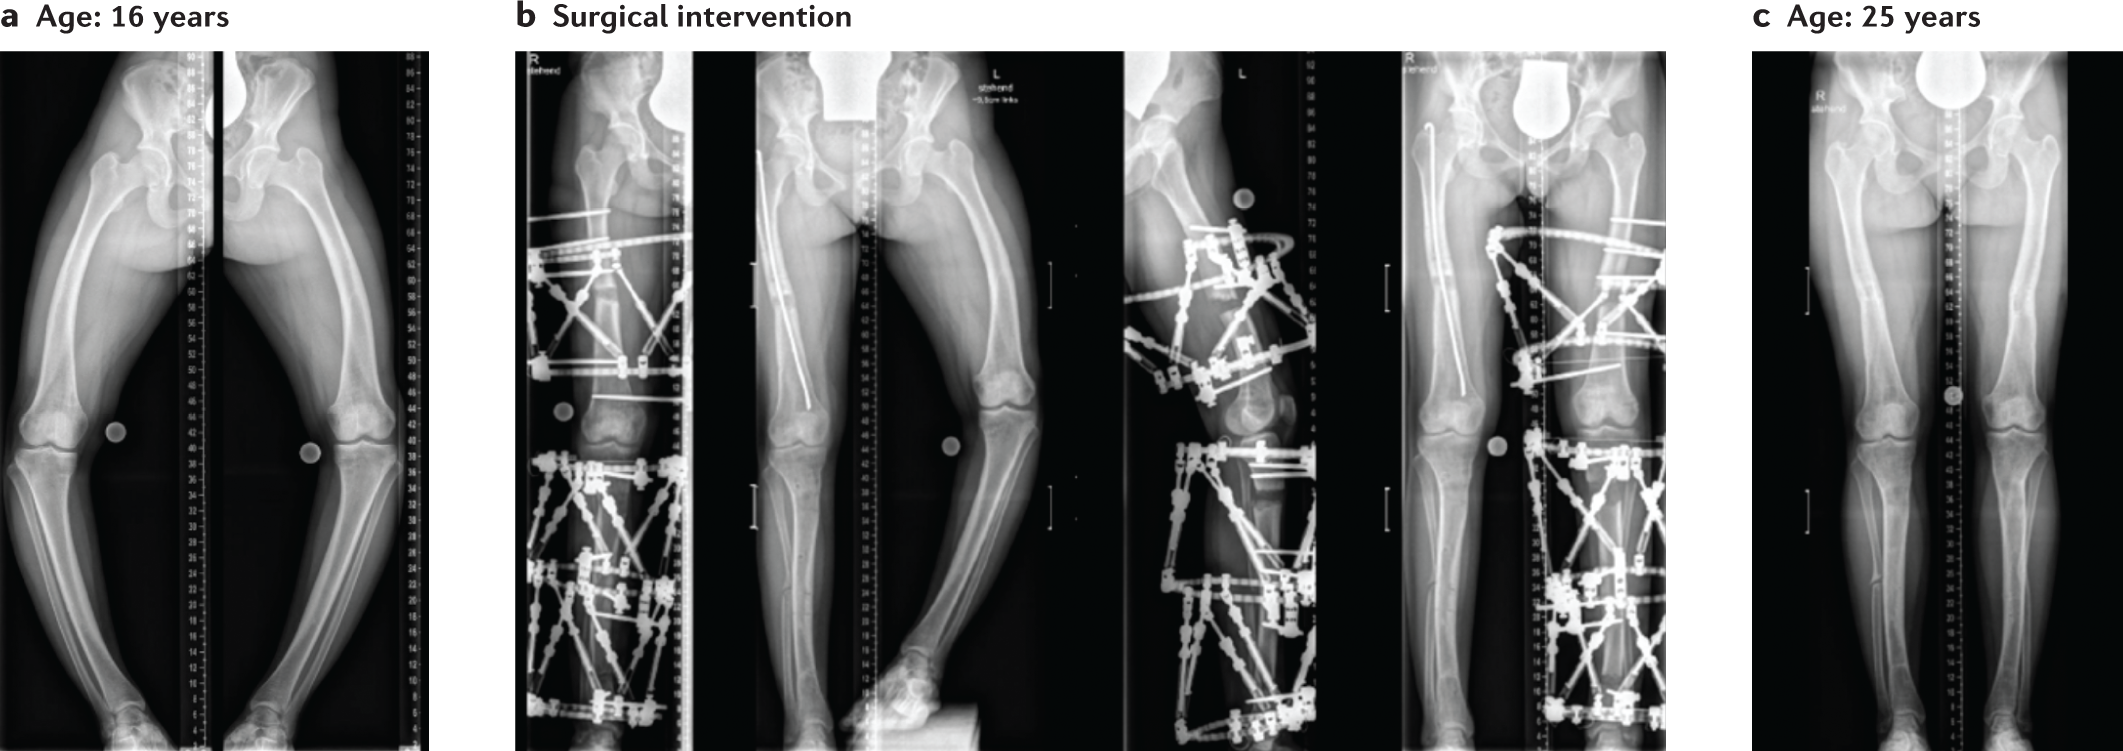

Fig. 1: Burden of XLH disease in an adolescent patient.

Radiographic images in a 16-year-old girl with X-linked hypophosphataemia (XLH)-associated rickets. The patient had sporadic disease with a confirmed PHEX pathogenic variant. Conventional therapy (oral phosphate supplements and calcitriol) was started in the second year of life. a | Severe and complex multi-apical varus deformity and maltorsion. b | Bilateral deformity correction and body height increase (9.5 cm) was achieved by performing multiple osteotomies and stabilization with external fixators (a Taylor Spatial Frame). c | Last follow-up at age 25 years (5 years after the last surgical procedure) with high patient satisfaction, high daily activity, no joint or muscle pains and excellent limb alignment. This patient illustrates the severity of bone deformities in XLH and the clinical efficacy of orthopaedic surgery in conjunction with conventional therapy. Image courtesy of C. Radler, Orthopaedic Hospital Speising, Vienna.